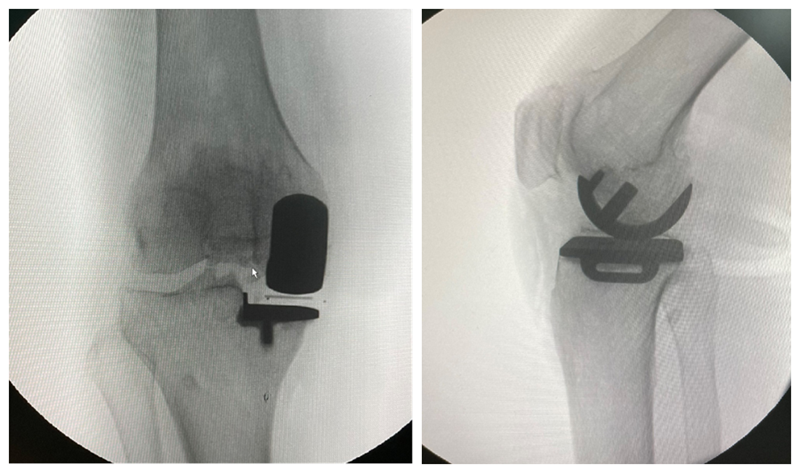

经典内侧单髁置换术(骨水泥型)

术前

术后检查

牛津单髁置换手术最经典的适应证是前内侧膝骨关节炎(AMOA),并且其他结构在功能上应保持完整,尤其强调韧带功能正常。在准备胫骨平台时,应保持7°后倾,截骨位置选在硬化骨下方,磨损最低点下方2mm处,近端紧贴,远端距皮缘18-20mm。试模间隙理想厚度6-7mm(包括胫骨假体3mm+垫片厚度3-4mm)。

在准备股骨侧时,理想状态为试模厚度刚好替换截骨厚度(约3mm),有5个关键点:(1)要保持韧带张力正常,避免过度松弛或过紧。(2)股骨假体位置保持良好,特别注意后髁截骨保持水平,去除骨赘,避免误判屈曲间隙。(3)股骨远端碾磨应保证内侧副韧带在屈膝110°和20°达到张力平衡。(4)要特别注意防撞击,保护内侧副韧带。(5)应采用2步法清除骨水泥。